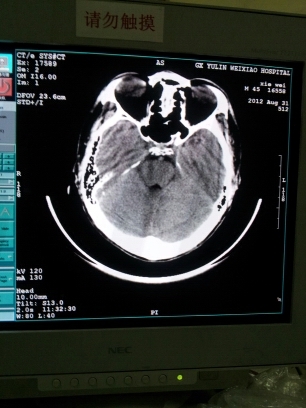

我院CT是GE 的CT-E的机器现在在做头颅时在图像下方出现半环伪影,定位没有伪影,断层扫描是才会有,在做其他部位时是没有的,只有在做头颅时才会出现的,请问各位高手这是什么问题?该怎么办,谢谢!! 20120901_162557.jpg

xbq 发表于 2012-9-2 22:43

我院CT是GE 的CT-E的机器现在在做头颅时在图像下方出现半环伪影,定位没有伪影,断层扫描是才会有,在做其他 ...

做过校正么? 要做水膜的那个哦! 如果不行可能要清理下滑环了

兄弟那是头托